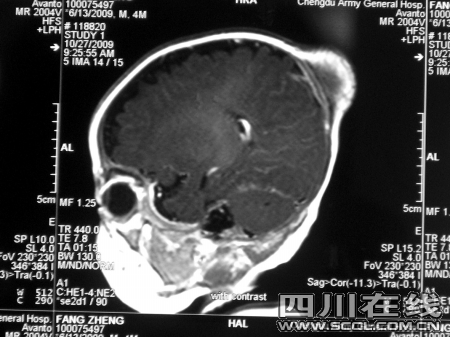

确诊婴儿患的是颅内外蔓状血管瘤

经过检查,确诊经经患的是颅内外蔓状血管瘤。该肿瘤靠近头顶大血管,

供血非常充足,手术难度非常大。“孩子太小,术中失血控制难度大,但肿瘤继续长大可能压迫脑组织和血管,造成头顶大血管破裂,威胁生命。”经过慎重考虑,神经外科请来麻醉科、小儿科和输血科会诊,共同确定手术方案。“我们不想让孩子失去最佳治疗时期。”